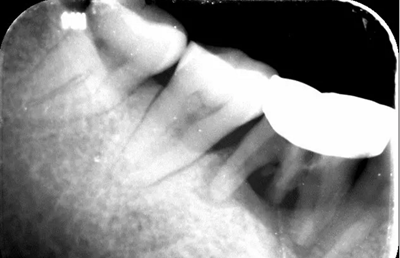

4、術(shù)前根尖片